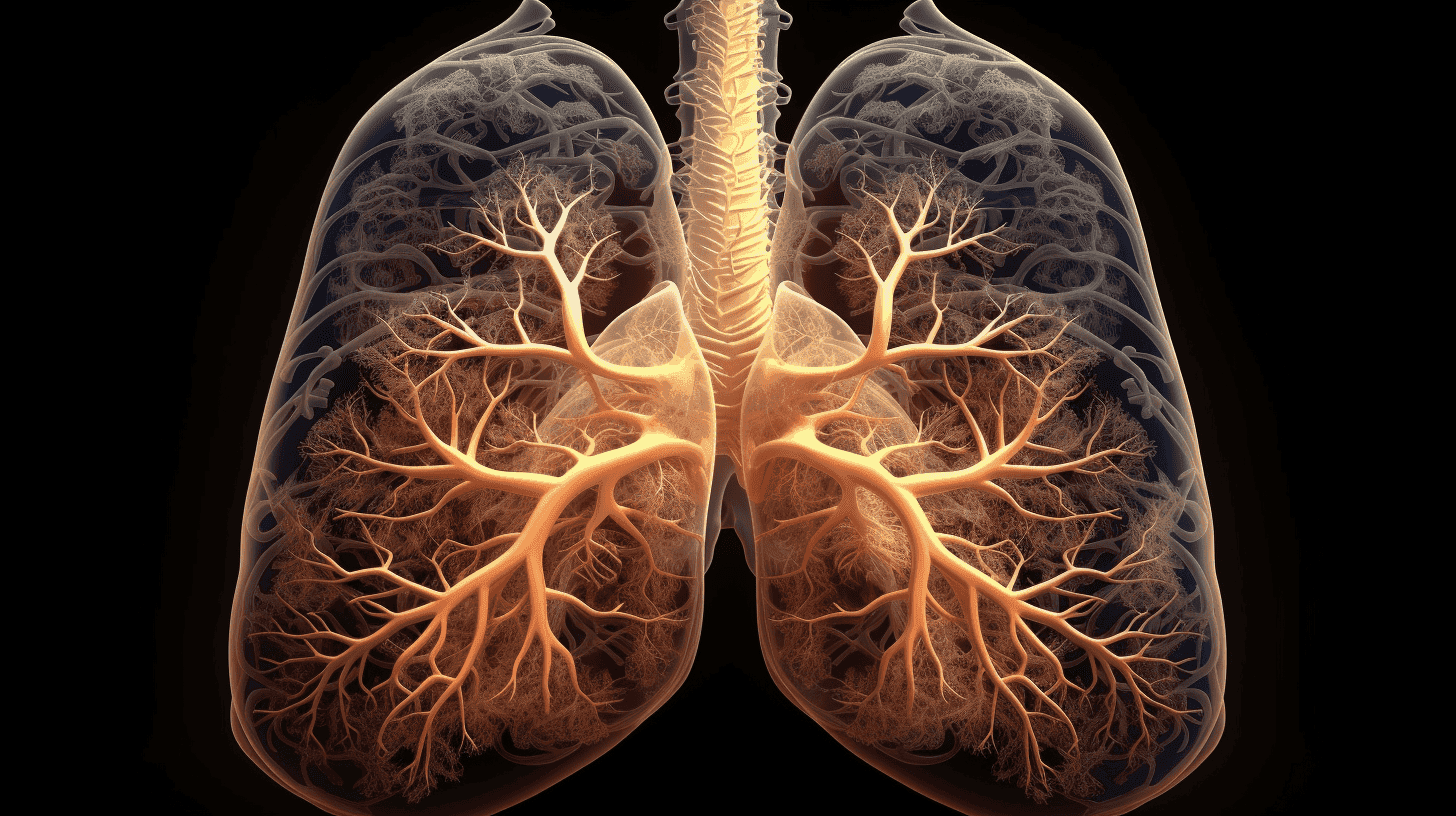

Thirona, a global leader specializing in advanced analysis of thoracic CT images using artificial intelligence, has received U.S. Food and Drug Administration (FDA) clearance for LungQ® 4, the latest version of its AI-powered CT analysis software.

This new clearance builds on version 3 of LungQ®, cleared by the FDA last year, which introduced advanced lung segmentation capabilities, a critical foundation for accurate regional-level analysis. LungQ® 4 extends these capabilities into:

• Enhanced peripheral airway segmentation.

• Estimated chronic perfusion defects from CT.

• Post-treatment detection of endobronchial implants.

Enhanced Peripheral Airway Segmentation

Leveraging Thirona’s FDA-cleared and CE-certified segmentation framework, along with advanced deep learning models, LungQ® 4 provides enhanced airway segmentation analysis, enabling identification of distal airways within previously inaccessible peripheral regions of the lung. By combining this extended analysis with anatomical airway mapping, LungQ® 4 delivers a detailed anatomical context that enhances clinical interpretation.

In navigational bronchoscopy, this can support precise access planning for distal airway targets in bronchoscopic interventions for the treatment of lung cancer, emphysema, and chronic airway diseases. In respiratory disease assessment, it can provide consistent anatomical referencing to visualize airway abnormalities up to the peripheral bronchial branches, enabling a clearer structural understanding of disease patterns within the bronchial tree.